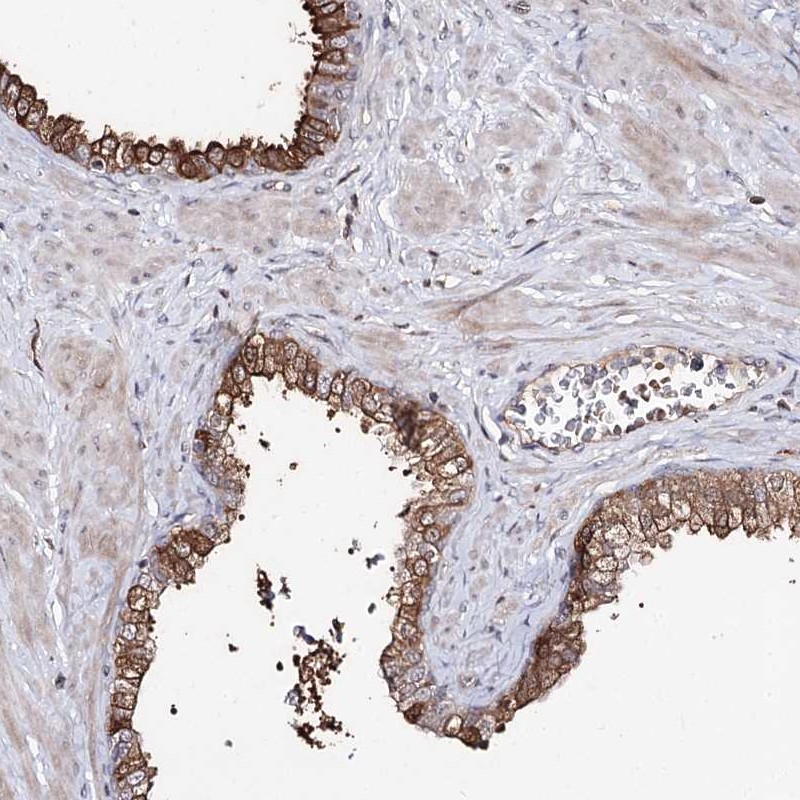

Immunohistochemical staining of human prostate shows moderate cytoplasmic positivity in glandular cells.